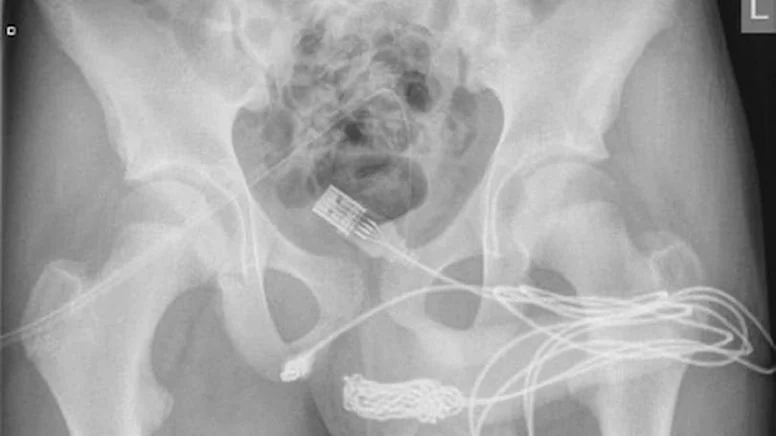

Ameliyatı gerçekleştiren doktorlar durumu kamuoyuna hazırladıkları bir rapor ile duyururken, USB kablolarının vücut içinde düğüm olduğunu ve bu sebeple ameliyatın büyük bir zorluk içerisinde gerçekleştiğini açıkladı.

Science Direct isimli medya platformunun Urology isimli bilimsel dergiden hazırladığı haberde yer alan bilimsel araştırmada olayın 2021’de meydana geldiği belirtildi. Doktorların kaleme aldığı bilimsel araştırmada, “Vücuda yerleştirilen cisim derin doku üzerinden çıkarıldı. Kablolar penis ucundan çıkarıldı” denilirken ismi açıklanmayan gencin cinsel deney için bunu yaptığı ve herhangi bir zihinsel rahatsızlığı olmadığı da duyuruldu